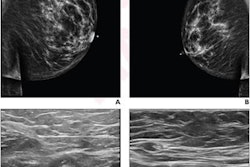

Ultrasound is used to assess lymph nodes before breast cancer surgery. Invasive techniques such as core-needle biopsy and ultrasound-guided fine-needle aspiration are used to confirm malignancies for suspicious nodes.

In the group's most recent study, the researchers wanted to find out the potential of similar AI techniques and image analysis in differentiating between malignant lymph nodes affected by breast cancer from benign nodes caused by COVID-19 vaccination.